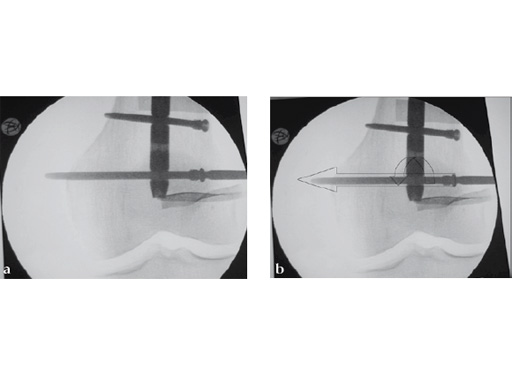

The screw-sleeve construct is pushed into the nail's locking hole by hand. For the final placement, a light hammer (100 gr) may be used (Fig 8). You can actually feel and even hear the correct positioning. Use of a heavier hammer may lead to too deep placement or even pushing the sleeve too far through the locking hole. Control by image intensifier of the reamer and/or screw placement is only needed in the very early part of the learning curve (Fig 9).